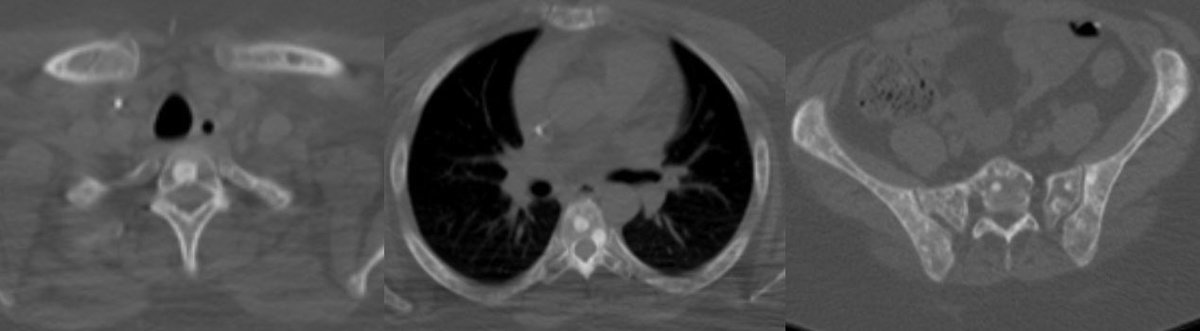

💡 Hypercellular tumor so DENSE on CT and DIFFUSION RESTRICTION (consistent feature)

▶️Hemorrhage is rare but calcifications seen in ~20%

💡 Most important job as a rad is to search for metastatic disease (leptomeningeal and systemic)!